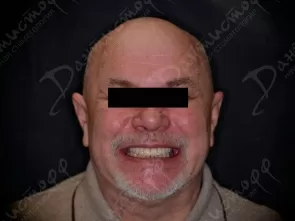

Фото работ